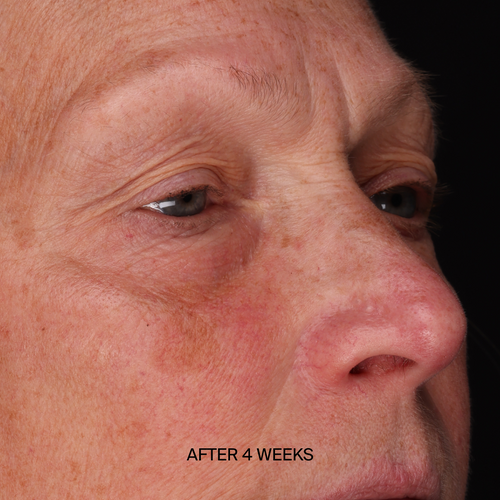

From cellular repair to dramatic, visible changes